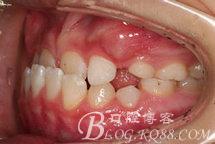

患兒,女性,10歲。

主訴:前牙反咬合(地包天)。曾經(jīng)有奶瓶喂養(yǎng)史。否認(rèn)家族遺史。

診 斷:安氏I類錯(cuò)合(III類傾向)。骨骼III類關(guān)系。凹面型:上頜劣生長(zhǎng)、下頜過(guò)生長(zhǎng)。上頜尖牙萌出間隙不足。前牙骨性反咬合。

方案:先使用帶低位唇弓的固定式的Actiator引導(dǎo)下頜向后,解除前牙反咬合。其后上頜使用2x4固定矯治器輕力唇移上頜切牙,開(kāi)劈間隙,為上頜其余牙齒的萌出創(chuàng)造條件,同時(shí)促使上頜生長(zhǎng)。

制作帶低位唇弓的Activator,將其粘結(jié)固定于上頜后牙。調(diào)節(jié)咬合面,解除前牙鎖結(jié)關(guān)系。U型曲加力引導(dǎo)下頜向后,反作用力也可促進(jìn)上頜向前生長(zhǎng)。